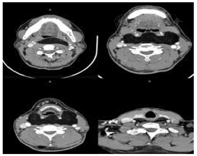

电子咽喉镜:鼻咽部黏膜光滑,咽后壁黏膜轻度充血,光滑,偏左侧平悬雍垂水平黏膜 隆起,下至环后区,挤压左侧梨状窝后壁,双侧梨状窝光滑,双侧声带光滑,运动对称。颈 部彩超:双侧颈部低回声,范围91 mm×31 mm (左侧),90 mm×23 mm (右侧) 边界清,双侧甲状腺受压下移,颈部CT(图2):咽后部、颈椎前方见不规则低密度影,边界清,组织内见分割影,最大截 面积89 mm×43 mm,平均CT值约-96HU,上达软腭水平,下达甲状腺水平,咽部诸结构均受压前 移,局部咽腔变窄,颈部强化CT:咽喉部肿物考虑脂肪性病变,实验室检查各项指标均大 致正常,肝胆胰脾及双肾输尿管彩超均未见异常。

马德龙Ⅰ型的诊断主要靠症状、体征和CT检查,其特殊体征为全身多处的皮下脂肪弥漫性、对称性的堆积,包块固定,无压痛,颈项部、枕部、腮腺区、刻下、下颌下、上肩部及胸骨、锁骨上窝多见,这些位置组织间隙多,所以早期可能无明显症状,随着脂肪堆积逐 渐增多,出现外观变化或各种压迫症状,如转颈及偏头受限,咽喉腔受压致吞咽、呼吸困难、睡眠打鼾等,压迫臂丛神经致上肢麻木、疼痛、抬肩无力等,根据症状涉及多科室,本患者就诊耳鼻喉科,是因为睡眠打鼾及吞咽阻挡感,颈部CT检查见整个咽旁间隙、咽后间隙见低密度影,贯通双侧颈部,组织内多分割影平均CT值约-96HU,考虑脂肪性病变,查阅文献得知此病的CT表现多为均一的脂肪组织密度影,内见大量条索状密度影,边界较清,临近 正常组织受压变形。